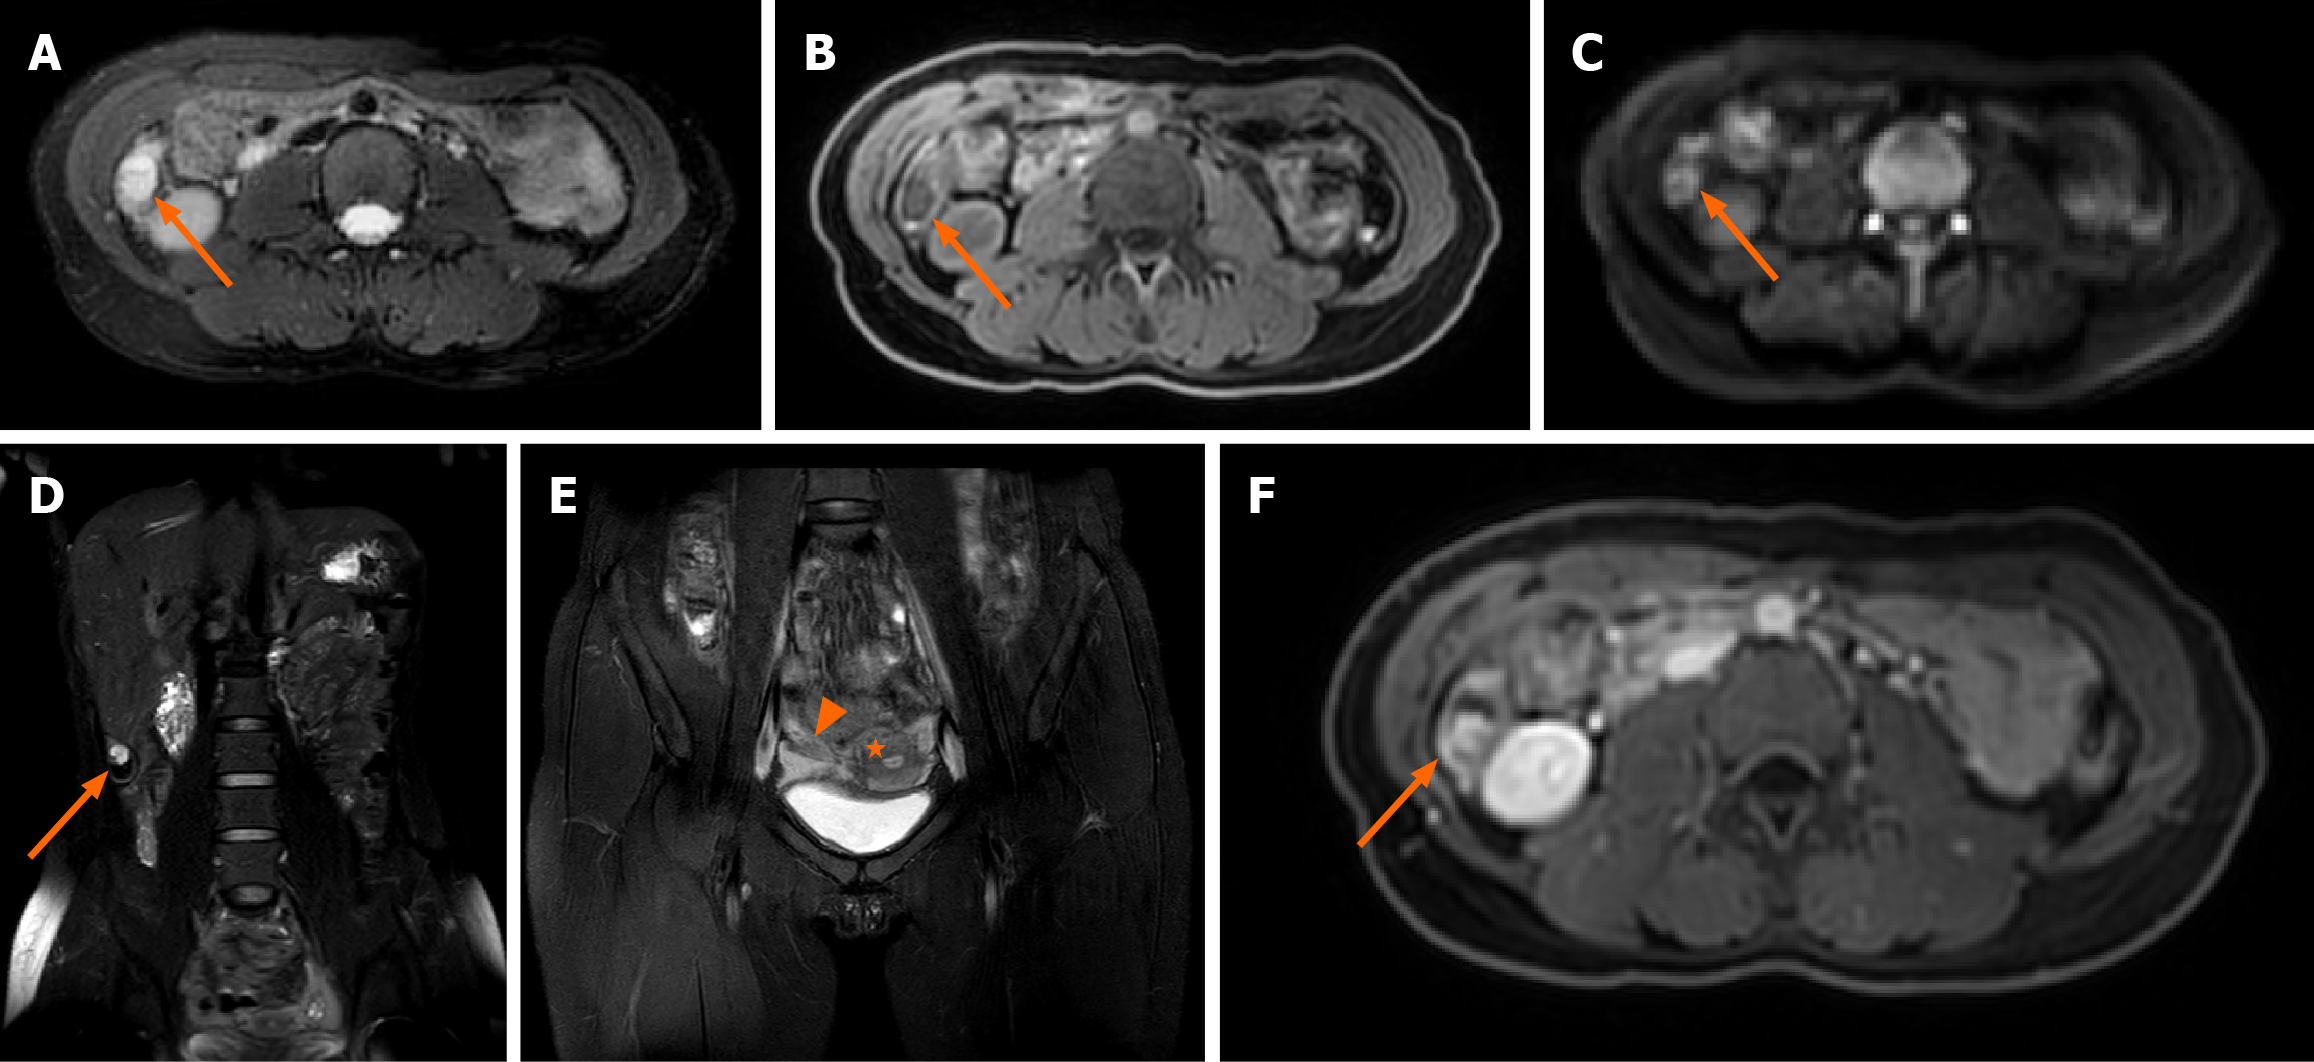

MRI of a 28-year-old pregnant woman with surgically and pathologically confirmed unruptured tubal ectopic pregnancy (Figure 1). Axial T2-weighted fat-suppressed image shows a small nodular hyperintense focus (arrow) within the gestational sac. Axial T1-weighted image demonstrates the nodule with isointense signal relative to muscle. Diffusion-weighted image (b-value = 800 s/mm²) shows no restricted diffusion within the lesion. The coronal magnetic resonance image of the entire abdomen shows that the gestational sac is located between the lower edge of the right lobe of the liver and the right iliac fossa. Coronal T2-weighted image confirms uterine morphology consistent with a left unicornuate uterus and a right rudimentary horn. The uterus is deviated toward the left pelvic sidewall. Axial contrast-enhanced T1-weighted fat-suppressed image reveals vivid enhancement of the nodule and mild enhancement of the cyst wall. Targeted transabdominal ultrasound, performed with MRI guidance, identifies the ectopic gestational sac in the right upper abdomen, within the subhepatic region (Figure 2). Intraoperative and histopathological correlation (Figure 3). Laparoscopic view showing a left unicornuate uterus and normal left ovary within the pelvic cavity. Intraoperative photograph shows the ectopic fallopian tube and ovary (arrow) displaced to the right upper abdomen, firmly adherent to the inferior hepatic surface and capsule.

Tubal ectopic pregnancy within an undescended right fallopian tube, associated with a left unicornuate uterus and a contralateral rudimentary horn.